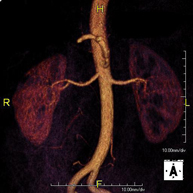

Prova diagnòstica no invasiva que consisteix en l'obtenció d'imatges d'alta definició anatòmica de tot el cos mitjançant l'ús d'un camp electromagnètic i ones de ràdio (amb un emissor i un receptor). No utilitza radiació ionitzant. És una prova molt important en la recerca de metàstasi en pacients amb neoplàsia coneguda. No requereix preparació prèvia. No és necessari l'ús de contrast paramagnètic (Gadolini). - Angio-RM d'Aorta abdominal

Prova diagnòstica no invasiva que consisteix en l'obtenció d'imatges d'alta definició anatòmica de tot el cos mitjançant l'ús d'un camp electromagnètic i ones de ràdio (amb un emissor i un receptor). No utilitza radiació ionitzant. És una prova molt important en la recerca de metàstasi en pacients amb neoplàsia coneguda. No requereix preparació prèvia. No és necessari l'ús de contrast paramagnètic (Gadolini). - Angio RM d'Aorta-ilíaca

Prova diagnòstica no invasiva que consisteix en l'estudi de l'artèria aorta abdominal i de les artèries ilíaques, amb l'obtenció d'imatges d'alta definició anatòmica mitjançant l'ús d'un camp electromagnètic i ones de ràdio (amb un emissor i un receptor). És indispensable l'ús de contrast paramagnètic (Gadolini). No utilitza radiació ionitzant. La qualitat de les imatges permet realitzar reconstruccions en 2D i 3D. Aquesta prova està especialment indicada com a estudi prequirúrgic (mapa vascular) abans d'intervencions percutànies o quirúrgiques d'aorta abdominal i artèries ilíaques, per a l'estudi complementari en pacients amb isquèmia de membres inferiors, etc. - Angio RM Arterial d'extremitats inferiors

Prova diagnòstica no invasiva que consisteix en l'obtenció d'imatges d'alta definició anatòmica de l'aorta toràcica (principal artèria del tòrax) mitjançant l'ús d'un camp electromagnètic i ones de ràdio (amb un emissor i un receptor). No utilitza radiació ionitzant. En la majoria dels casos és necessari l'ús de contrast paramagnètic (Gadolini). Permet un estudi angiogràfic no invasiu gràcies a la injecció de Gadolini amb posterior reconstrucció en 2D i 3D, mitjançant estacions de treball especialitzades. També inclou l'estudi de la vàlvula aòrtica, informació imprescindible en el cas que el pacient necessiti cirurgia. Aquesta prova està especialment indicada en pacients que requereixen tractament quirúrgic (com a mapa vascular prequirúrgic), en el seguiment de pacients amb aneurismes d'aorta, etc. - Angio-RM d'Aorta Abdominal

Prova diagnòstica no invasiva que consisteix en l'estudi de l'artèria aorta abdominal per obtenir imatges d'alta definició anatòmica mitjançant l'ús d'un camp electromagnètic i ones de ràdio (amb un emissor i un receptor). És indispensable l'ús de contrast intravenós paramagnètic (Gadolini). No obstant, no utilitza radiació ionitzant. La qualitat de les imatges permet realitzar reconstruccions en 2D i 3D. Està indicat en aquells pacients amb malaltia vascular (Aterosclerosi), per a l'estudi d'aneurismes, en estudis prequirúrgics de lesions adjacents a l'aorta abdominal com "mapa" vascular, etc. - Angio-RM Aorta ilíaca

Prova diagnòstica no invasiva que consisteix en l'estudi de l'artèria aorta abdominal per obtenir imatges d'alta definició anatòmica mitjançant l'ús d'un camp electromagnètic i ones de ràdio (amb un emissor i un receptor). És indispensable l'ús de contrast intravenós paramagnètic (Gadolini). No obstant, no utilitza radiació ionitzant. La qualitat de les imatges permet realitzar reconstruccions en 2D i 3D. Aquesta prova està especialment indicada com estudi prequirúrgic (mapa vascular) abans d'intervencions percutànies o quirúrgiques d'aorta abdominal, per a l'estudi complementari en pacients amb isquèmia de membres inferiors, etc. - Angio-RM d'Artèries renals